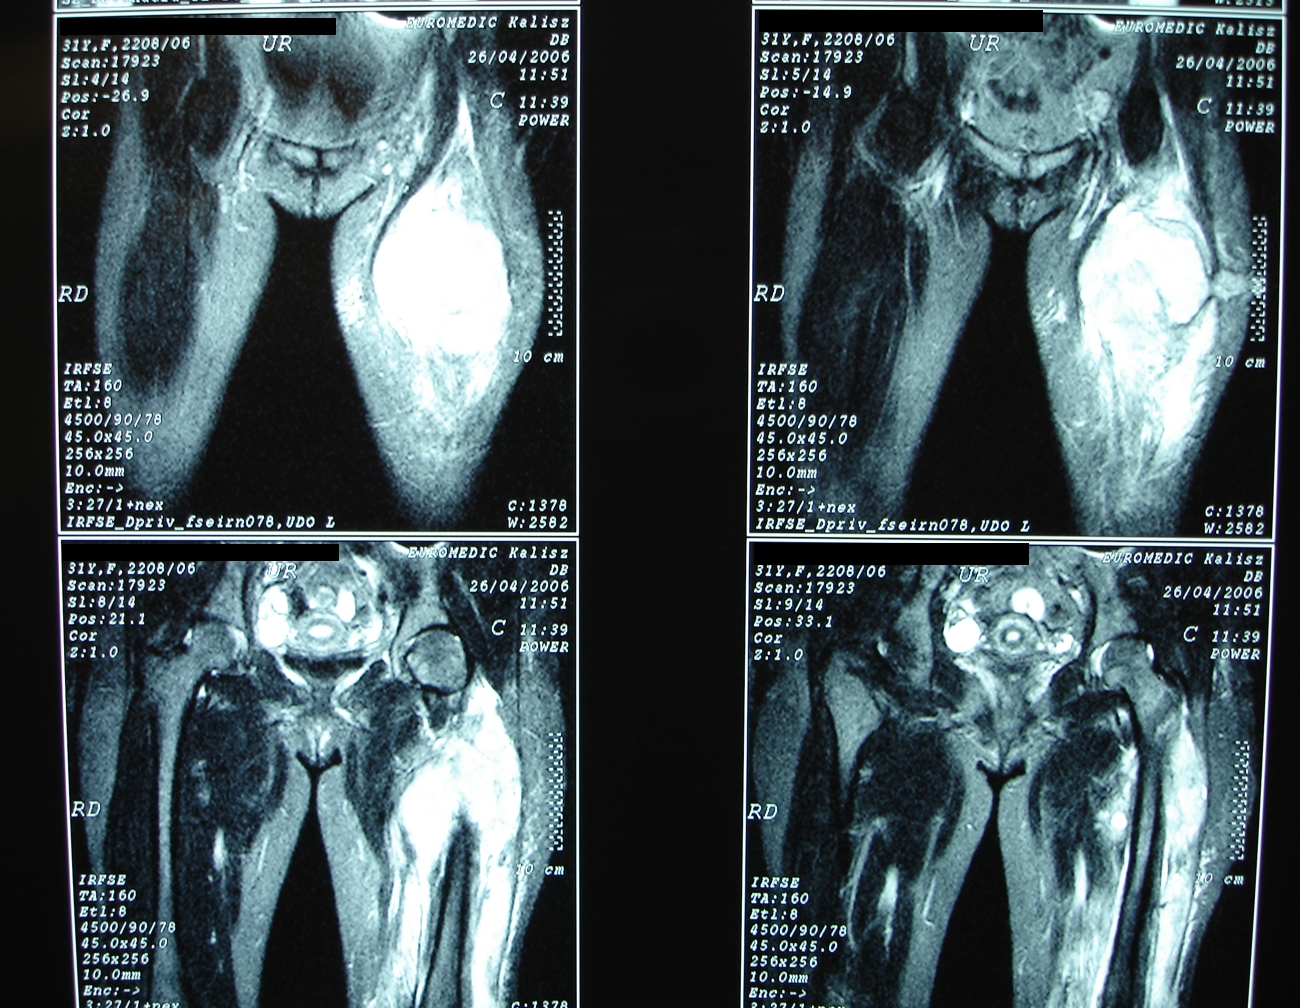

Po usunięciu guza - elastyczne aplikatory są mocowane w loży guza

Wszystkie aplikatory na miejscu